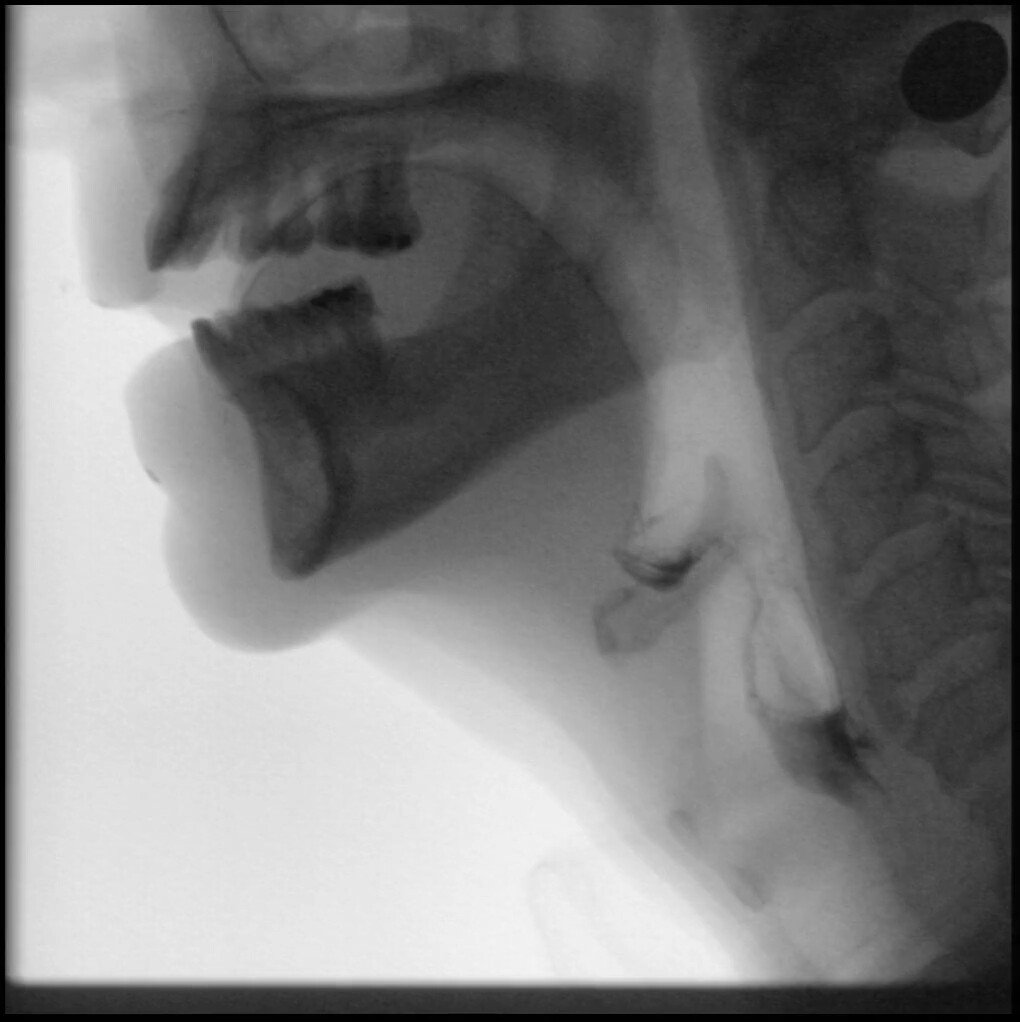

Simultaneously record your fluoroscopic or endoscopic studies while capturing live footage in the evaluation room. Review the results of compensatory strategies, patient reactions to given stimuli, the pros/cons of various techniques, and more.